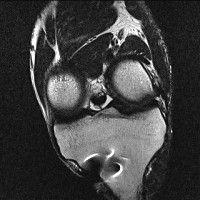

무릎 mri 간단히 봐주실 수 있으시나요 ㅠㅠ

안녕하세요 8년전 십자인대 수술하고 최근 무리한 운동에 무릎 불편감이 생겨서

mri 찍었습니다.

진단결과는 첫 찍은 병원에서 활액막염 이라는 진단을 받았습니다. 혹시 봐주실 수 있으실까요?

올라온 MRI가 단편적이라서 정확한 진단에 어려움이 있지만 십자인대에는 큰 이상이 있지는 않은것 같으며, 무릎관절내 물이 있는 것으로 보아 활액막염의 진단이 맞을 것 같습니다.

하지만 단편적인 영상이기 때문에 촬영병원에서 정확한 판독지 등을 받으시는 것이 좋겠습니다.